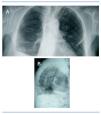

Figura 1. Radiografía de tórax posteroanterior (A) y lateral (B), donde se visualiza imagen radiopaca filiforme en el hilio pulmonar izquierdo, correspondiente a la cubierta de PTFE de la guía metálica del catéter Arrow Cannon II Plus®.